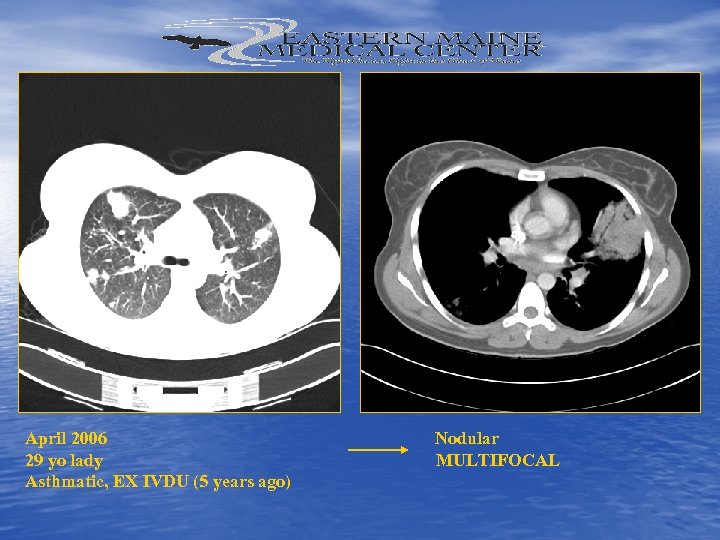

April 2006 Nodular 29 yo lady MULTIFOCAL Asthmatic, EX IVDU (5 years ago)

April 2006 Nodular 29 yo lady MULTIFOCAL Asthmatic, EX IVDU (5 years ago)